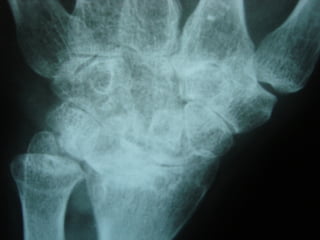

Achados radiográficosAchados radiográficos

 Osteopenia peri-articularOsteopenia peri-articular

 Diminuição do espaço articularDiminuição do espaço articular

 Presença de cisto e erosõesPresença de cisto e erosões

 Edema de partes molesEdema de partes moles

 Presença de deformidadesPresença de deformidades

1- osteopenia 2-erosões 3-sub-luxação